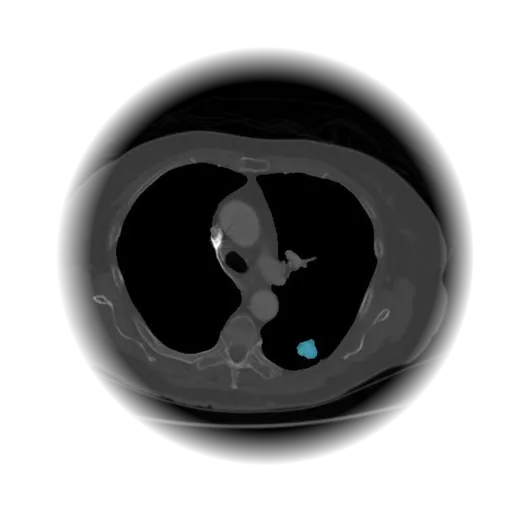

Lung Nodule Detection and Tracing Across Scans

Obvios.ai utilizes cutting-edge artificial intelligence to meticulously detect and track lung nodules, facilitating swift and precise diagnostics, thereby ensuring superior care and timely intervention for patients.